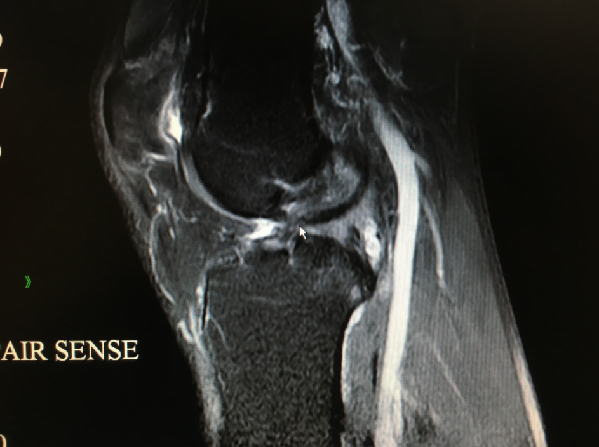

核磁共振检查发现,他的前叉韧带已经吸收消失,半月板也发生了退变磨损。上周,南医三院关节外科运动医学科副主任曾春为其重建了韧带,修整半月板等,目前恢复良好。不过,要想激烈运动,可就要等到两年后了。

南医三院院长蔡道章在为他查体的时候,一拉他的左腿,就说“应该是前叉断了”。核磁共振拍片确认前叉韧带断裂后,赵先生很懊悔,“觉得对自己很不负责任。”